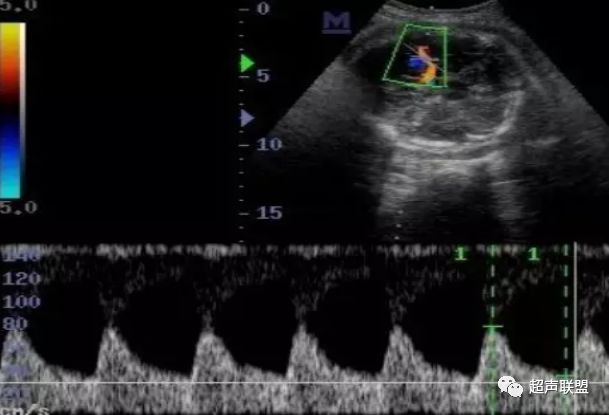

图2 脐动脉舒张期血流消失或反向